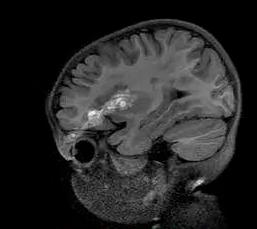

近日,福建3岁女童小美在家玩回弹软轴乒乓球时,玩具上的不锈钢软轴竟不慎插入了孩子的左眼上方!

入院一查,诊断结果吓坏了不少人:开放性颅脑损伤、颅内少量血肿、左眼眶上壁骨折伴左眼眶周围软组织挫裂伤。

医生说:“万幸不锈钢软轴只是从眼球边上擦过,没造成眼球破裂。但还是出现了玻璃体积血,孩子后期视力可能会受影响。”